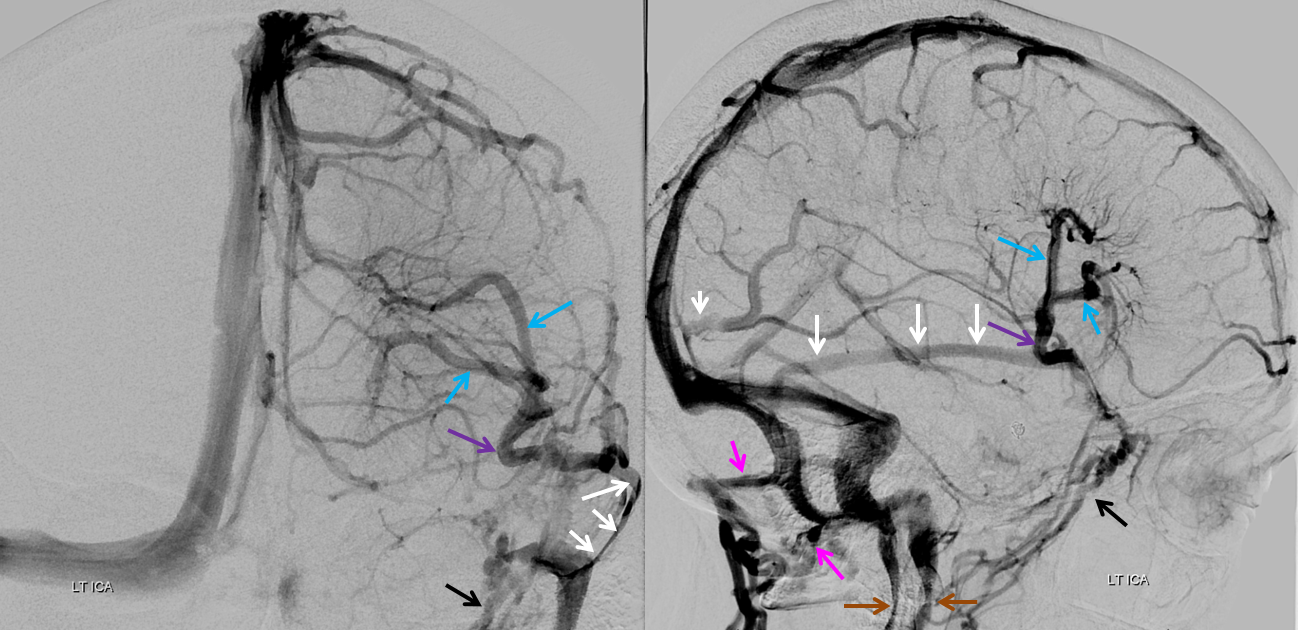

Some arrows. Open white arrows — septal veins on the medial aspect of frontal horn. Thick white arrows — longitudinal caudate venous arcade. Black arrow — direct lateral vein, prominent because of hypoplasia of the posterior segment of the left longitudinal caudate vein. Thin white arrows are transverse/ medullary veins

Sagittal Sinus Thrombosis — collaterals.

All of the above anatomic knowledge can become very useful in evaluation of venous thrombosis. Numerous collateral pathways develop in this setting attempting to compensate for the loss. The most dramatic cases usually involve the largest channel — the superior sagittal sinus. In this case, a man presented with what initially was thought to be vasculitis-related brain hemorrhage. Subsequent workup led to an angiogram, where sagittal sinus thrombosis with extensive trans-cerebral and trans-osseous emissary vein collateral channels was seen. In retrospect, these findings were present on the patient’s earlier contrast MRI. “Venovibe” or other contrast-enhanced MR venograms can very sensitive, particularly when interpreted with the appropriate index of suspicion. Noncontrast 2-D time of flight MRV I consider to be next to useless as a problem-solving technique. Any thin-slice postcontrast T1 study is vastly superior.